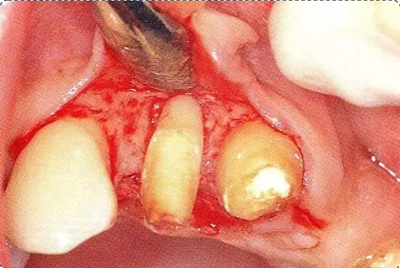

深牙周袋的治療

圖10-3  考慮到審美性,應(yīng)用牙齦乳頭保存術(shù)(Papilla preservation technique),進(jìn)行了自體骨移植。

圖10-4  骨缺損部位進(jìn)行骨修整結(jié)束的狀態(tài)。